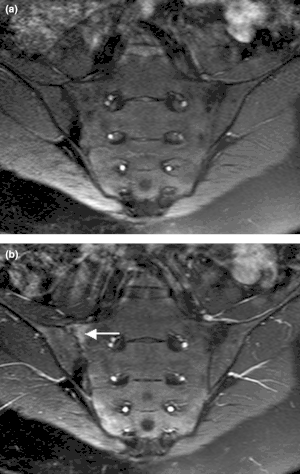

Magnetic resonance images of sacroiliac joints. Shown are T1-weighted semi-coronal magnetic resonance images through the sacroiliac joints (a) before and (b) after intravenous contrast injection. Enhancement is seen at the right sacroiliac joint (arrow, left side of the image), indicating active sacroiliitis. -